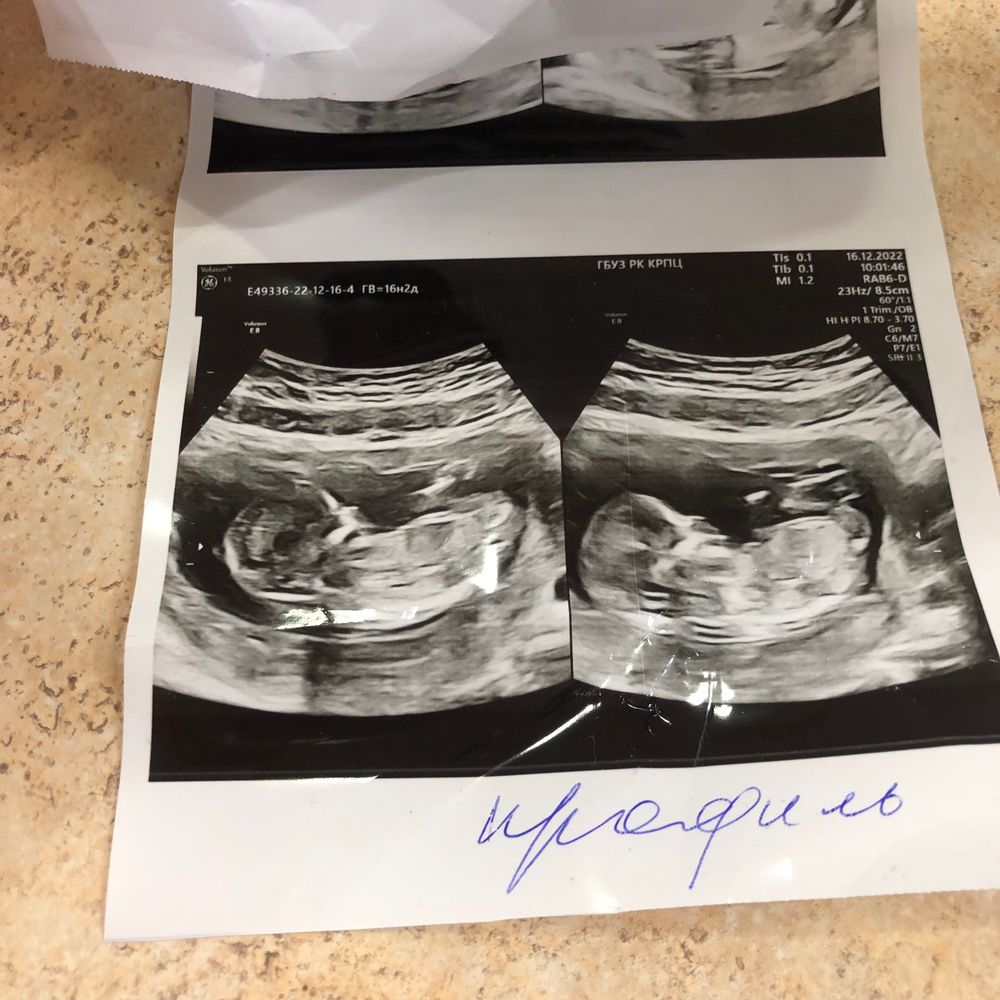

Пророчат девочку , но вот этот 1%)

Все привет мне пророчат доченьку , у кого есть опыт в узи , срок 13,2 ❤️🤞 мы конечно будем рады любому исходу но дочка как приятный бонус 😍🍀 всем заранее спасибо ☺️